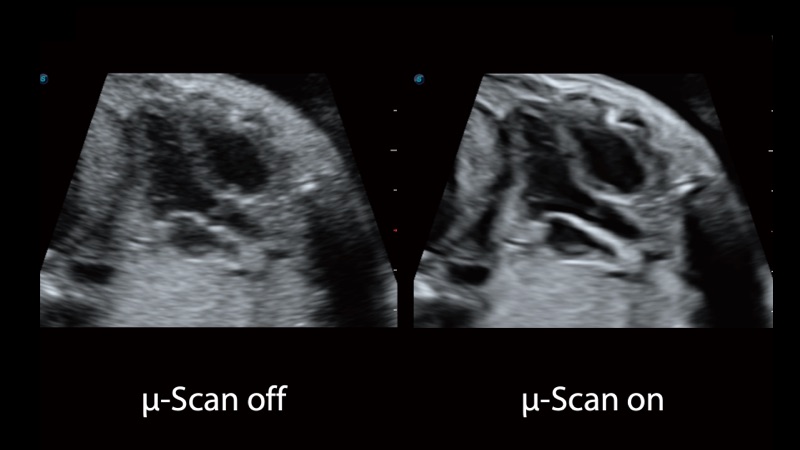

開立醫(yī)療通過不斷的技術(shù)創(chuàng)新,為大眾的生命健康提供持續(xù)關(guān)愛。P12 Plus采用全新一代超聲成像平臺,新平臺旨在將真實(shí)還原組織解剖結(jié)構(gòu)作為首要目標(biāo)。平臺采用全新集成化硬件模塊,搭載新一代芯片,系統(tǒng)性能得到大幅提升,為您的診斷提供了豐富的臨床信息。優(yōu)異的圖像表現(xiàn),豐富的探頭配置,全面的應(yīng)用功能,為您日常診斷提供了可靠的助手。

彩色多普勒超聲診斷系統(tǒng)